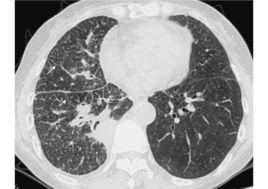

CT表現

肺血管增粗、支氣管壁增厚、小葉間隔及胸膜增厚,並可使這些組織邊緣表現為不規則、結節狀或串珠狀。Johkoh等將其CT表現分為三型:

1.軸心間質增生為主:從肺門到周圍肺野可見血管或/和支氣管壁增粗增厚,甚至可見小葉核心增粗,少見或者不見小葉間隔增寬;

2.周圍間質增厚為主:小葉間隔增寬為突出表現,呈條狀垂直於胸壁或連成長條狀,在肺的中心部分可見因小葉間隔增寬而襯托出多邊形的小葉輪廓,少見或者不見有軸心間質增厚現象;

3.軸心間質及周圍間質增厚都有。

CT能清晰顯示肺血管及支氣管壁的病變徵象,尤其是高解析度CT(HRCT)能顯示小葉核心及葉間胸膜的增厚和增粗,進而全面顯示每一病例肺部病變的詳細情況。